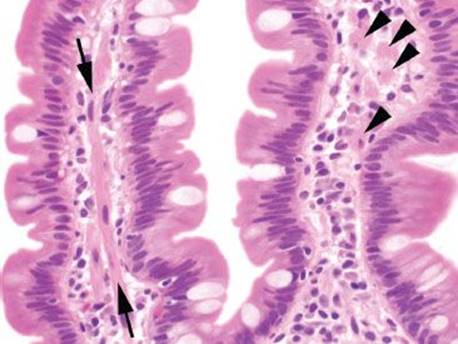

The villous epithelium is lined by tall columnar absorptive epithelial cells, each of which contains an apical brush border composed of microvilli (Figs. 3.6–3.8). These minute projections further augment the surface area of the small bowel. Interspersed between the absorptive cells are goblet cells, which secrete both neutral and acid mucins. These sialomucins stain blue-purple on a combined Alcian blue-PAS stain. Scattered endocrine cells are present within the villous epithelium, but they are more abundant within the crypts. Intraepithelial lymphocytes (IELs) are normally present as one per five epithelial cells. The deep crypts additionally contain abundant Paneth cells (Fig. 3.9). The lamina propria rests on the muscularis mucosae, surrounds the crypts, and extends upward into the core of the intestinal villi. It serves as an immunologic organ and contains plasma cells, lymphocytes, eosinophils, histiocytes, and mast cells. Plasma cells are the most abundant cellular lamina propria constituent. Most contain IgA but some contain IgM; in contrast to their abundance in extraintestinal sites, IgG secreting plasma cells are scarce. Lymphocytes of both B- and T-lineage are common. The only granulocytes normally found in the lamina propria are eosinophils and mast cells. The muscularis mucosae is composed of a thin layer of smooth muscle cells separating the mucosa from the underlying submucosa. Tufts of smooth muscle radiate from the muscularis mucosae into the lamina propria and extend into the villi (Figs. 3.10–3.12).

Figure 3.10 Normal small bowel, smooth muscle within villous core. Delicate tufts of smooth muscle (arrows) extend from the muscularis mucosae along the core of the villi. When cut in cross section (arrowheads), these can be mistaken for histiocytes, signet ring cell carcinoma, or infectious diseases (such as Mycobacterium avium intracellulare).

Figure 3.11 Normal small bowel, normal variant morphology in small intestine. Remember that the slide is a two-dimensional representation of three-dimensional tissues. Villi may be truncated if they extend out of the plane of section, as seen here. The adjoining long, slender villi reassure observers that there is not true villous atrophy.